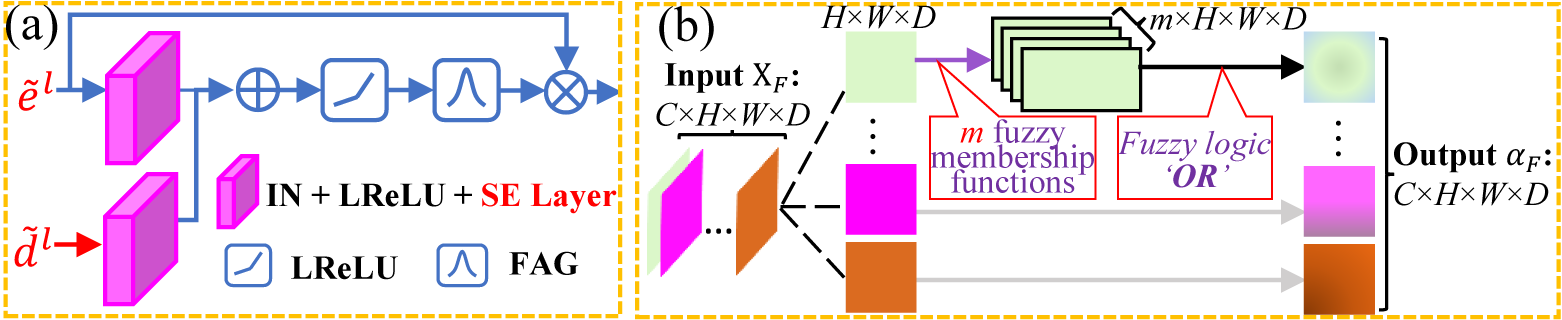

One of the key challenges to design a robust lung organ segmentation module lies in the inherent uncertainty from the organ annotations and voxel values, e.g., bronchioles and arterioles. Various efforts have been done to enhance the network to focus on pertinent regions. Notably, Attention U-Net [12] introduces an attention gate to bolster accuracy by suppressing feature activations in irrelevant regions. However, we deem that the non-channel specifics of current attention map assign the same “attention” coefficient to all feature points along the channel dimension. Specifically, given a feature map , the extant attention map is built as , while all features along the channel wise C share the same “importance”. This mechanism is unreliable since the features in different channels are extracted by different convolution kernels; therefore, we advocate the attention map to be channel-specific.

Meanwhile, numerous studies have proved the efficacy of both fuzzy logic and neural networks in data representation [10]. Broadly speaking, neural networks strive to diminish noise in original data to extract meaningful feature representations, while fuzzy logic can derive fuzzy representations, mitigating the original data uncertainty. Hence, we fuse fuzzy logic with attention mechanism by utilizing trainable Gaussian membership functions (GMFs). This fusion serves to enhance the segmentation network’s ability to focus on pertinent regions, concurrently diminishing uncertainty and variations in data representations.

As shown in Fig. 4(a), the proposed efficient fuzzy attention module is adopted within the skip connection, taking both feature maps {, } from the l-th encoder and decoder layers as inputs, which are directly yielded by the transformer-like 4 expansion/compression layers in ConvNeXt [20] backbone, followed by an instance normalization and a Leaky-ReLU layers for feature reconstitution. Then, two very lightweight squeeze-excitation (SE) layers [5] are employed to further boost the channel-specificity. Next, a voxel-wise adding operation is adopted to fuse the information, followed by a Leaky-ReLU. Eventually, the feature representations are fed into the FAG to generate a voxel-wise attention map, shown in Fig. 4(b). Assume (regardless of batch size) as the input of FAG. Due to the smoothness and concise notation of GMFs, learnable GMFs are proposed to specify the deep fuzzy sets. Each feature map (with size ) is filtered by GMFs with the trainable centre and spread

| (1) |

where . Our goal is to use the membership function to learn the “importance” of target fuzzy feature representations. Given the trade-off of model efficiency & efficacy, GMFs are used. Thus, we assume that the information can be better preserved by applying the aggregation operator “OR” while suppressing irrelevant features. Given fuzzy sets and , the operator “OR” is denoted as Equ. 2(a).

| (2) |

where U is the universe of information and is the element of U. To make the operator “OR” derivative, we modified it as Equ. 2(b). Then, the fuzzy degree of the -th channel can be obtained based on Equ. (1) and Equ. (2) as

| (3) |

where indicates the union operation. Finally, the output tensor of proposed FAG has the same shape as input , providing a voxel-wise attention map .